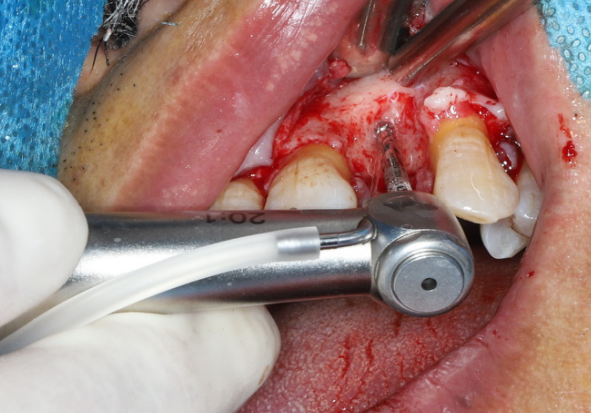

采用不切开骨膜的软组织扩张术——Soft Tissue Extend释放软组织张力

记录翻瓣后原始软组织瓣长度,使用软组织搔刮器(Soft Tissue Extender)冠根向搔刮软组织瓣。

在不切断骨膜的前提下,使用软组织刮治器反复搔刮软组织瓣,可以起到延长软组织瓣的作用。

使用软组织搔刮扩张前后对比:可见在不切断骨膜的前提下,使用软组织搔刮即可获得软组织瓣延长8-9mm。